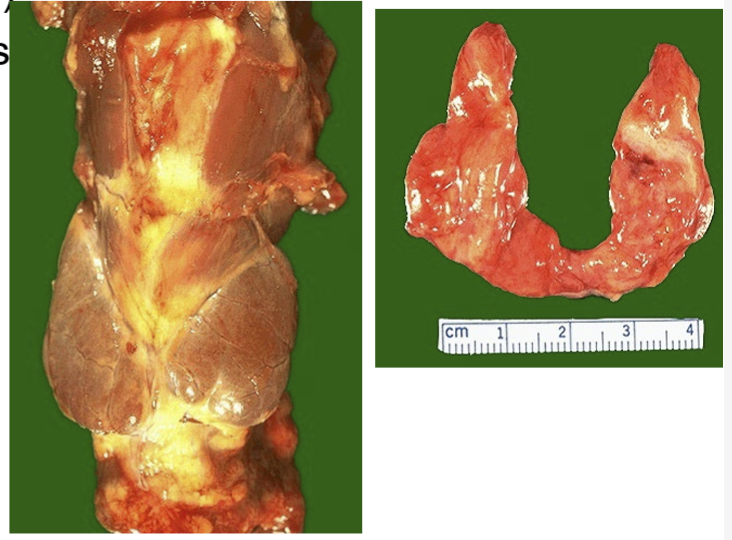

What disease is this

Hashimoto’s disease